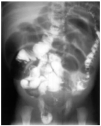

Síndrome de obstrucción intestinal